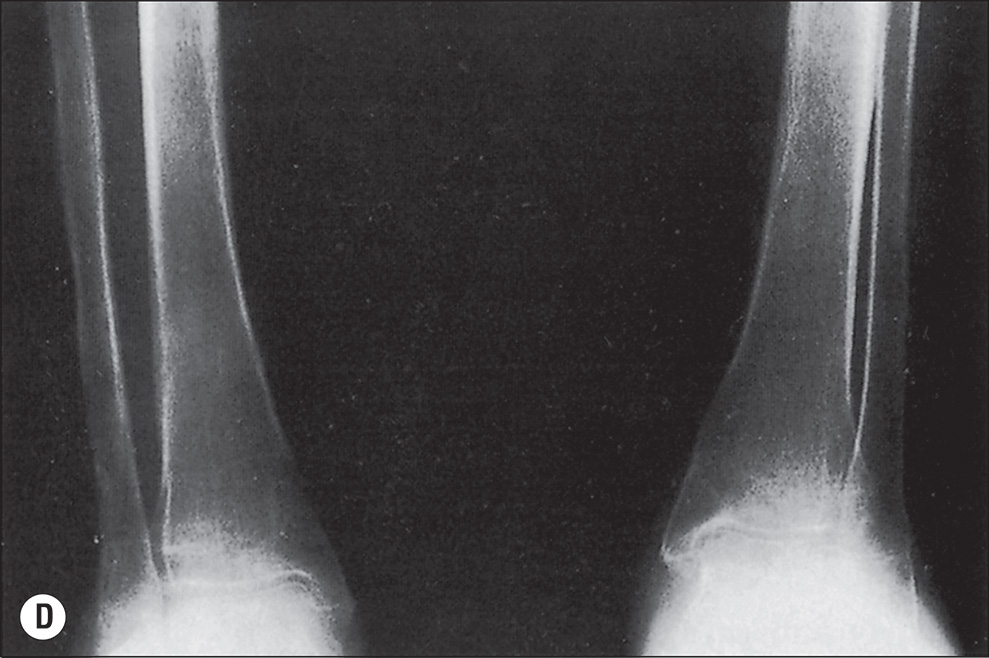

The more extensive the burn and the greater the number of complications, the longer the patient may be confined to bed and relatively immobile. The onset of osteoporosis is accelerated, and its intensity is more marked in the burn illness that features a hypermetabolic state. Klein et al. found that osteoblasts and probably osteocytes underwent apoptosis in response to the glucocorticoid stress hormones. The overall effect of burn is catabolic, and muscle wasting is also noted. If a single extremity of an otherwise normal person is immobilized for a long time because of local trauma, as with a fracture, loss of bone density can be easily seen on plain radiographs. So, with burns isolated to the extremities, the bones of affected extremities become osteoporotic, and in persons with generalized burns, the bones of deeply burned extremities may show more profound mineral loss than is observed in nonburned extremities or in the axial skeleton ( Fig. 41.1 ). This tendency for more osteoporosis in severe burns was also noted by Pandit et al., who found that 56% of postburn patients had radiographic evidence of osteopenia. Van der Wiel et al. found in an x-ray absorptiometry study of 16 adults with fractures of one tibia that there was eventual loss of bone mineral density in the contralateral femur and in the lumbar spine but to a lesser degree than in the ipsilateral femur. These findings, although not strictly analogous to those observed in burns, nevertheless point to the occurrence of generalized osteoporosis in other trauma states and the difference in loss of bone density relative to local factors. In fractures or in burns, impaired mobility and local hyperemia could account for this difference.

(A) Advanced osteoporosis in the hands of a 14-year-old boy 9 months after a 100% total body surface area burn. All growth plates are open. (B) At 24 months after injury, osteoporosis persists, and there is irregular closure of the metacarpal and phalangeal growth plates. (C) At 8 months after injury, the growth plates of the distal tibiae and fibulae remain open. (D) At 24 months after injury, the distal growth plates of the tibiae and fibulae are closed. Other major growth plates remain open. Osteoporosis is unchanged.